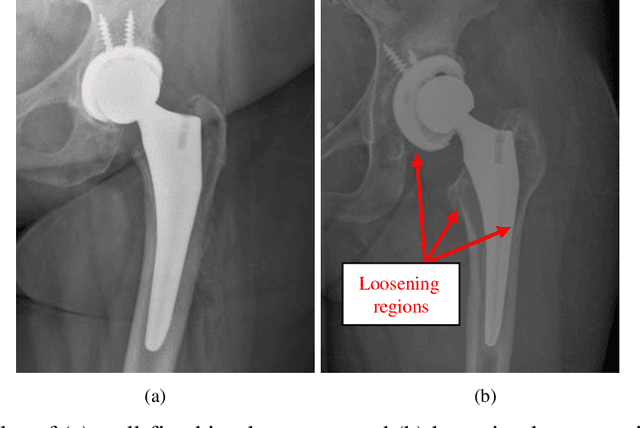

Abstract:Plain radiography is widely used to detect mechanical loosening of total hip replacement (THR) implants. Currently, radiographs are assessed manually by medical professionals, which may be prone to poor inter and intra observer reliability and low accuracy. Furthermore, manual detection of mechanical loosening of THR implants requires experienced clinicians who might not always be readily available, potentially resulting in delayed diagnosis. In this study, we present a novel, fully automatic and interpretable approach to detect mechanical loosening of THR implants from plain radiographs using deep convolutional neural network (CNN). We trained a CNN on 40 patients anteroposterior hip x rays using five fold cross validation and compared its performance with a high volume board certified orthopaedic surgeon (AFC). To increase the confidence in the machine outcome, we also implemented saliency maps to visualize where the CNN looked at to make a diagnosis. CNN outperformed the orthopaedic surgeon in diagnosing mechanical loosening of THR implants achieving significantly higher sensitively (0.94) than the orthopaedic surgeon (0.53) with the same specificity (0.96). The saliency maps showed that the CNN looked at clinically relevant features to make a diagnosis. Such CNNs can be used for automatic radiologic assessment of mechanical loosening of THR implants to supplement the practitioners decision making process, increasing their diagnostic accuracy, and freeing them to engage in more patient centric care.